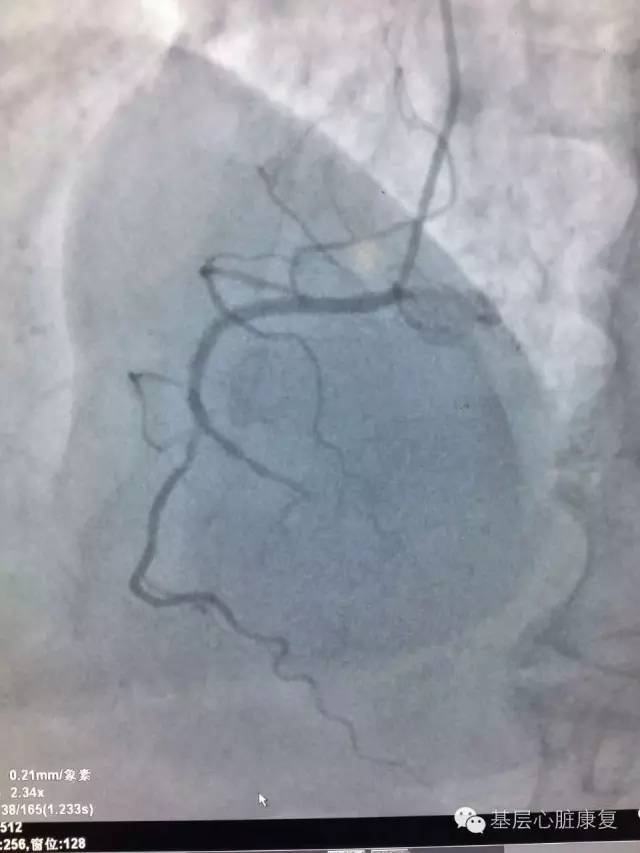

安阳地区医院心内一科收治一位65岁男性患者,一个月前冠状动脉造影示前降支70%狭窄,回旋支50%狭窄,右冠脉100%闭塞。仅右冠需要血运重建,为冠状动脉介入治疗适应症。曾于一月前行右冠状动脉介入治疗,因导丝进入假腔,未能通过闭塞病变,手术未成功。

汗水湿透了手术衣而浑然不知,厚重的铅衣未能压垮必胜的信念。忘记了时间,忘记了疲劳,忘记了家里的老小。面对复杂的器械和病变,脑子时刻清晰不能有一丝混乱,心中的执着不能有一点懈怠。眼睛紧盯屏幕捕捉每一刻的影像,手中的钢丝在IVUS指导下探寻着通往光明的每一丝线索, 直至导丝穿入真腔并沿真腔前进,到达远端血管病变。